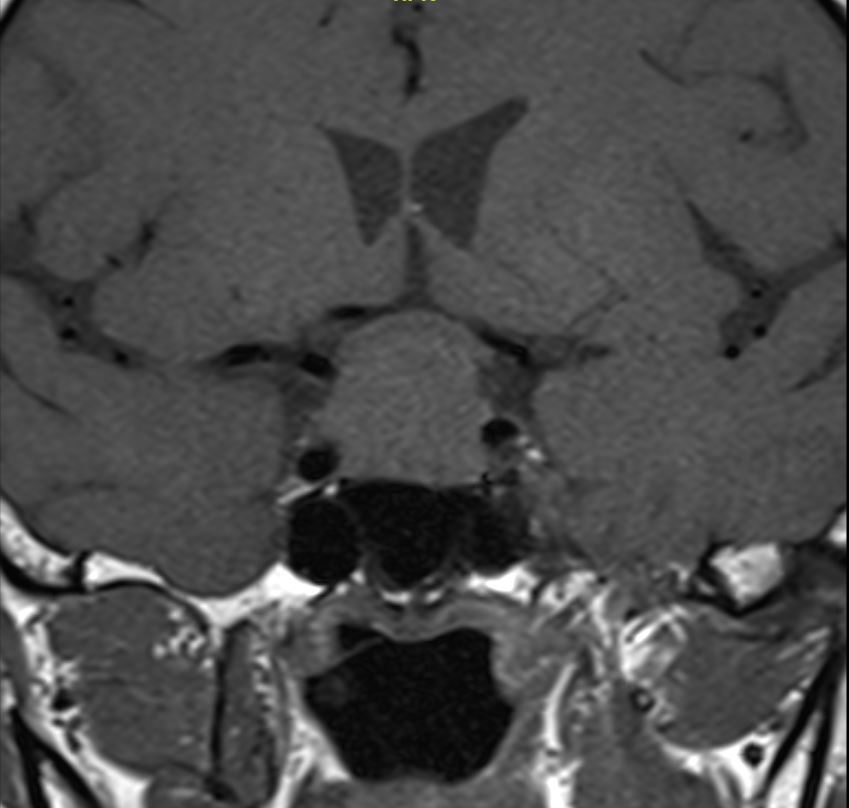

患者为63岁患者,因头痛伴有视物模糊2个月前来就诊,检查头颅MRI检查发现鞍区占位性病变,肿瘤大小2.3cm,向上生长压迫视交叉,两侧侵犯海绵窦。

增强冠状位